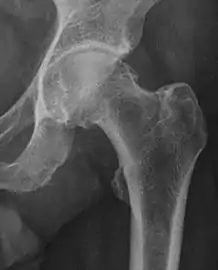

Projectional radiography ("X-ray")is often considered first line for FAI.[10] Anterior-posterior pelvis and a lateral image of the hip in question should be attained.[10] A 45-degree Dunn view is also recommended.[10][19]

| Crossing ratio | ![]() |

Percentage of acetabular walls crossing. Normal acetabulum is oriented in anteversion. Its value ranges from 15 to 20° in the equatorial plane of the acetabulum and decreases gradually towards the acetabular roof, where normal values range from 0 to 5°. Retroversion of the upper part of the acetabulum has been related with pincer type impingement. In radiography the presence of a "crossover sign" is produced when the posterior wall of the acetabulum crosses the anterior wall before reaching the acetabular roof. It is a sign of acetabular retroversion and it has been linked with overcoverage and pincer impingement. Nevertheless, this sign has been described in 6% of the normal population. Therefore, more important than its presence is the percentage of crossing. | <20%

|